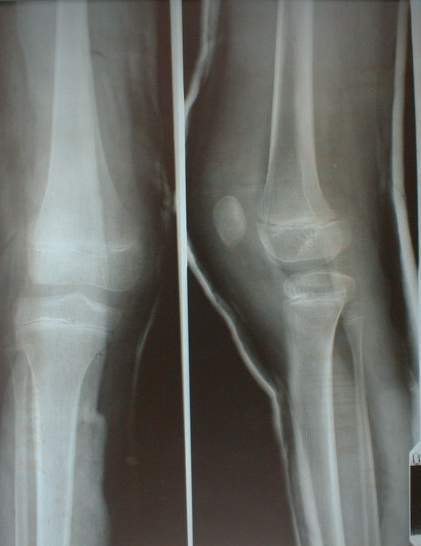

您的位置首页百科问答 先天性髌骨脱位 Simone 发布于 2025-09-28 19:15:30 858 阅读 先天性髌骨脱位的有关信息介绍如下:先天性髌骨脱位又称先天性髌骨外侧脱位,多为双侧,是出生后即可见到的一种较为罕见的新生儿畸形。想要了解更多“先天性髌骨脱位”的信息,请点击:先天性髌骨脱位百科